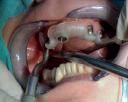

Raţiunea asigurării unei armonii biologice este completată de criterii tehnice ce ghidează laboratorul în cursul fabricării unei restaurări dentare estetice şi funcţionale. Totuşi, ceea ce nu se înţelege întotdeauna în laborator este faptul că limitările anatomice oferă adesea cea mai mare valoare predictivă pentru integrarea estetică a unei restaurări implantare anterioare.

Pentru a maximiza estetica restaurărilor implantare frontale, etapa iniţială a planului de tratament include integrarea protezei în zâmbetul pacientului, în conformitate cu limitările anatomice ale pacientului.

Acest articol examinează rolul bontului în susţinerea succesului estetic şi tehnic. Sunt incluse discuţii cu privire la restaurările cimentate vs fixate cu şurub, selecţia materialului pentru substituţia dintelui frontal şi parametrii designului.

Atunci când conform obiectivului, implanturile se plasează la nivelul sau uşor sub nivelul osului şi la cel puţin 2mm de peretele vestibular, există ţesut moale generos şi spaţiu vertical amplu pentru ca tehnicianul să dezvolte contururile de emergenţă ce îndeplinesc criteriile ce urmează a fi discutate în prezentul articol.

Dacă însă implanturile sunt plasate prea vestibular sau prea superficial, componentele nu permit un design adecvat al bontului, pentru că plasarea marginii este limitată iar conturul facial şi proximal poate fi compromis (fig. 1, 2).

Deşi în acest articol sunt prezentate criteriile pentru fabricarea bontului implantar, este important de menţionat că integrarea zâmbetului pacientului este determinantă înainte de inserarea implantului, iar rolul bontului

în susţinerea esteticii este limitat de procesul de planificare a tratamentului pentru restaurarea finală (fig. 3-5).